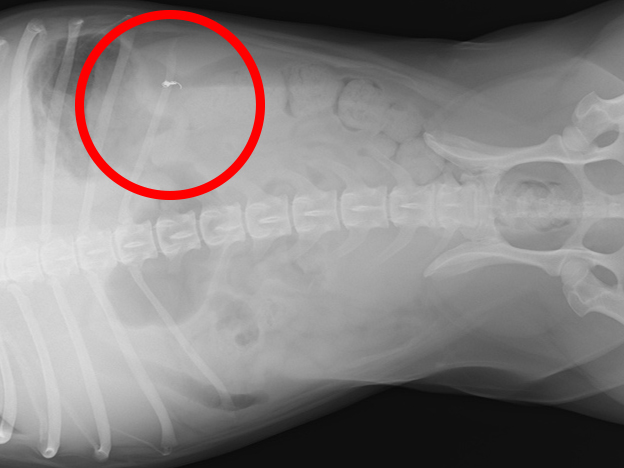

術後2ヶ月後のレントゲン写真(赤丸がコイル)